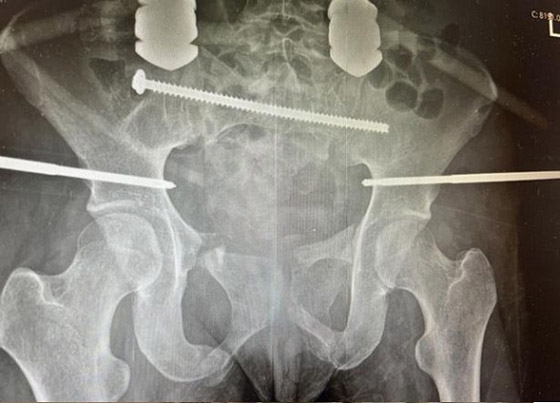

نجت ممرضة متدربة بريطانية بأعجوبة بعد سقوطها من لعبة في مدينة الملاهي مما أدى إلى قطعها إلى نصفين تقريبا. وأعطى الأطباء كلوي أوستن (21 عاماً) نسبة 0% للنجاة من الحادثة المروعة التي تركتها مع كسور مفتوحة متعددة في ساقها اليمنى وحوضها في أغسطس (آب) من العام الماضي. وأمضت كلوي من مدينة بارو 22 يوماً في غيبوبة، وخضعت لعدة عمليات جراحية منقذة للحياة قبل أن تتعافى، لكنها اضطرت لتعلم المشي من جديد.

وأوضحت كارين هاورث، مديرة خدمة الصدمات الرئيسية في مستشفى رويال بريستون، لانكشاير، أن خروج كلوي من المستشفى كان معجزة مطلقة، بعد تعرضها لأسوأ كسر في الحوض يمكن أن يصاب به أي شخص. وقالت كلوي في حديث لصحيفة ميرور البريطانية "عندما استيقظت لم أستطع تذكر أي شيء ، لم أتذكر حتى الذهاب إلى أرض المعارض، ظللت أفكر في أنني لا بد أنني تعرضت لحادث سيارة. عندما أخبرني الأطباء أنني لن أمشي مرة أخرى على الأرجح، ربما كان ذلك من أصعب الأمور التي اضطررت للتعامل معها".

ورفضت كلوي قبول هذا المصير، ووضعت لنفسها هدفاً جعلها في النهاية قادرة على الحركة بعد أربعة أشهر ظلت خلالها مقيدة بالسرير. وقالت كارين هوورث من رويال بريستون إن العاملين في مستشفى فورنيس العام حيث نُقلت كلوي لأول مرة اعتقدوا أنها ستموت هناك. وساد نفس الشعور عندما وصلت كلوي إلى قسم الطوارئ في بريستون أيضاً لكنها رفضت التوقف عن محاربة ما كان يمكن أن يصبح بسهولة إصابات قاتلة. كلوي، التي كانت في طريقها للتأهل كممرضة قبل أن تخرج دراستها عن مسارها بسبب الإصابات التي تهدد حياتها، وضعت نصب عينيها العمل في نفس مركز الصدمات الرئيسي الذي أنقذها.